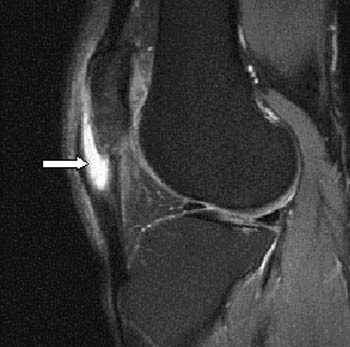

베이커 낭종 또는 슬와 낭종은 반막근(semimembranosus)과 비복근(gastrocnemius)의 내측두의 힘줄 사이의 슬관절 후방으로 이어져 있는 점액낭이다. (그림 46-5) 베이커 낭종의 존재는 만성적이거나 재발하는 슬관절 삼출액을 암시하고 특히 반월판 파열과 연골 결손과 같은 관절내의 병소를 찾도록 하는 징후이다.

△ 그림 46-5. 베이커 낭종. 반월판의 레벨을 통과하는 축면 지방 포화 T2 강조 시퀀스

베이커 낭종은 반막근건(화살표)과 비복근건의 내측두(별표) 사이에서 확대된 것으로 보인다. 외측과 비교하여 내측 반월판이 정상적으로 더 큰 표면적을 가짐을 또한 주목할 것. M = 내측, L = 외측